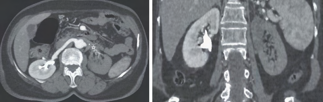

Recent studies indicate that Generative Pre-trained Transformer 4 with Vision (GPT-4V) outperforms human physicians in medical challenge tasks. However, these evaluations primarily focused on the accuracy of multi-choice questions alone. Our study extends the current scope by conducting a comprehensive analysis of GPT-4V's rationales of image comprehension, recall of medical knowledge, and step-by-step multimodal reasoning when solving New England Journal of Medicine (NEJM) Image Challenges - an imaging quiz designed to test the knowledge and diagnostic capabilities of medical professionals. Evaluation results confirmed that GPT-4V outperforms human physicians regarding multi-choice accuracy (88.0% vs. 77.0%, p=0.034). GPT-4V also performs well in cases where physicians incorrectly answer, with over 80% accuracy. However, we discovered that GPT-4V frequently presents flawed rationales in cases where it makes the correct final choices (27.3%), most prominent in image comprehension (21.6%). Regardless of GPT-4V's high accuracy in multi-choice questions, our findings emphasize the necessity for further in-depth evaluations of its rationales before integrating such models into clinical workflows.